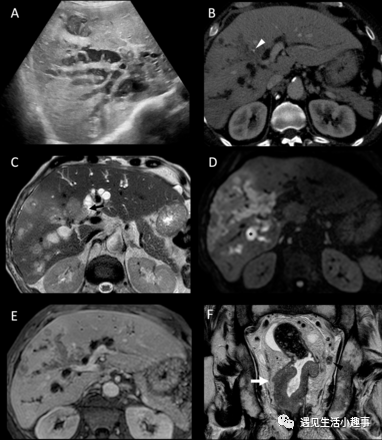

一名65岁男性,既往无特殊病史,因厌食、黄疸和发热症状到急诊科就诊。 血清总胆红素水平为7.5 mg/dL,直接胆红素为5.4 mg/dL。 腹部超声检测到肝内胆管广泛且不规则扩张,内容物不均匀,显示在一级胆管汇合处突然终止,被一个边界不清的低回声病变所掩盖(图1A)。 CT证实左右胆管汇合处存在边界不清的病变,浸润性生长和门脉增厚,尤其是在右叶(图1B)。还发现中低直肠壁不规则增厚,疑似肿瘤。 磁共振胰胆管造影显示血供不足的病变,沿胆管扩散和浸润性生长受限,与导管内乳头状突起相关,涉及汇合处、右导管和右前导管(图1C-E)。 在对特征为腺癌的直肠病变进行活检时,进行直肠MRI检查,将肿瘤分期为T3N1(图1F)。 癌胚抗原和CA19.9分别升高至14.9 ng/mL和47.5 U/mL。 图1:(A)腹部超声检测到肝内胆管广泛和不规则扩张,内容物不均匀,以及相关的肝内异质液体聚集,提示肝脓肿。胆管汇合处被一个界限不清的低回声病变所掩盖。(B)腹部CT门静脉期证实在胆管汇合处存在边界不清的血供不足病变,沿右前胆管扩张和浸润性生长,门静脉通道增厚。在肿块中发现点状钙化(白色箭头)。(C)腹部MRI[T2加权图像(WI)轴平面]。肿块有导管内生长,表现为乳头状突起(黑色箭头)。(D)腹部MRI(弥散WI;b=900)。在病变中心和沿右前胆管发现扩散受限,表明胆管内生长。此图像中还存在肝脓肿(星号)。(E)腹显示与CT的相同发现。保留门静脉和分支。(F)直肠MRI(T2-WI冠状)对浸润右侧直肠系膜脂肪(白色箭头)并邻接内括约肌但不侵入括约肌间平面的直肠肿瘤进行分期。还发现了一个可疑淋巴结(黑色箭头)。(F)直肠MRI(T2-WI冠状)对浸润右侧直肠系膜脂肪(白色箭头)并邻接内括约肌但不侵入括约肌间平面的直肠肿瘤进行分期。还发现了一个可疑淋巴结(黑色箭头)。